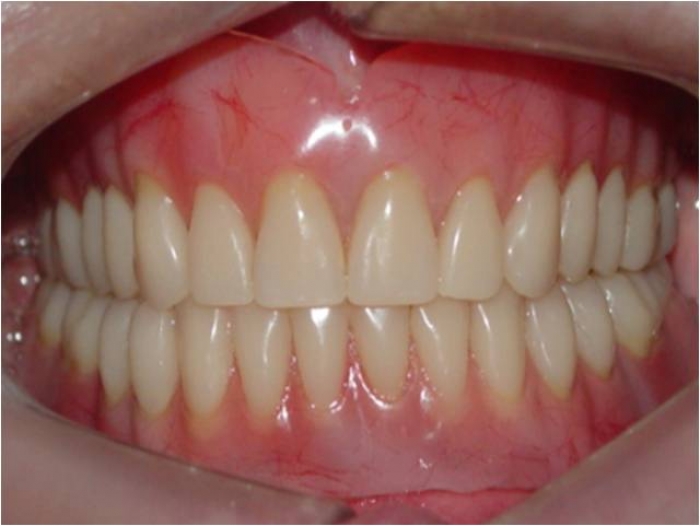

Sorriso final, do caso terminado em janeiro de 2014